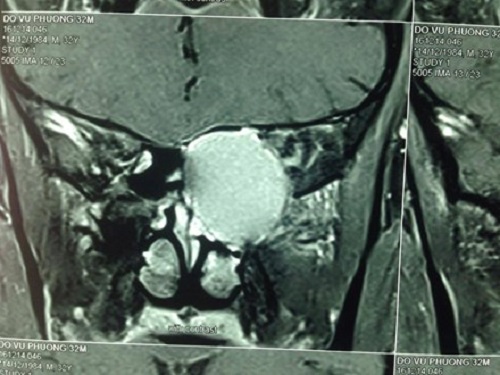

Hình ảnh chụp khối u nhầy vùng sàng sau huỷ xương và chèn ép thần kinh thị giác (ảnh BS Hớn) Ảnh Lao Động. |

Báo Lao Động cũng đưa tin cho biết thêm, tại Bệnh viện Tai Mũi Họng, bệnh nhân được thăm khám, chụp CT và phát hiện khối u nhầy (mucocele) vùng sàng sau huỷ xương, chèn ép thần kinh thị. Bệnh nhận được phẫu thuật cấp cứu trong đêm, dẫn lưu khối u nhầy.